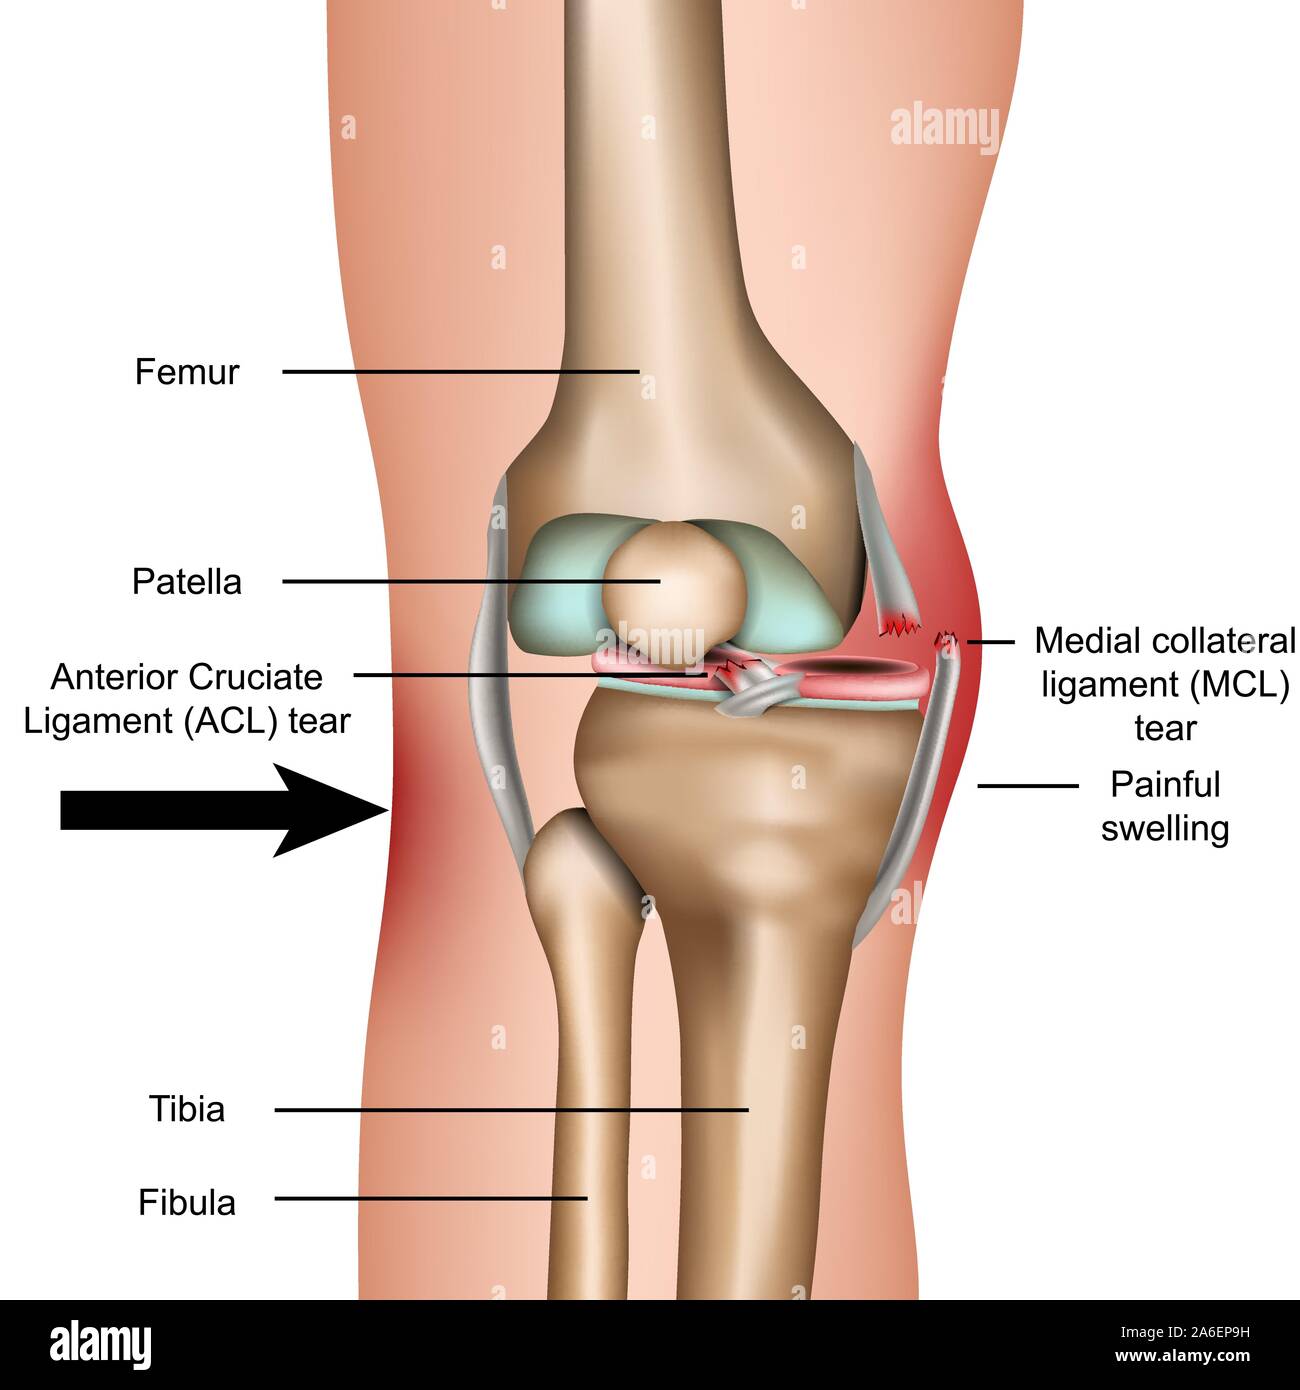

Строение коленного сустава. Повреждения мениска. Разрыв крестообразной связки. Гончаров Е.Н.